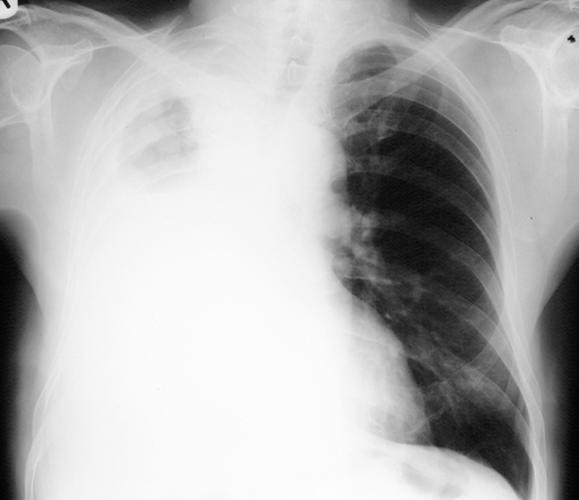

https://cdn.ncbi.nlm.nih.gov/pmc/blobs/bb85/2001143/0365e0429ea8/umj7602-065-f1.jpg